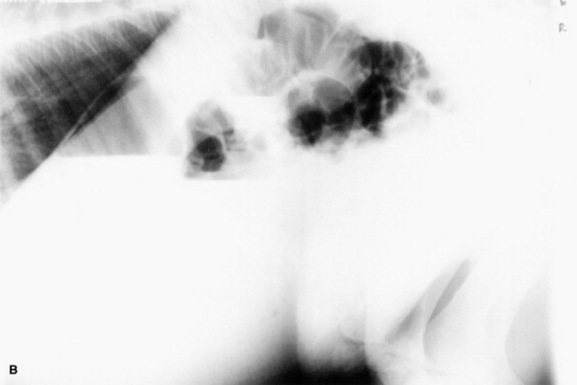

Serial thoracic radiographs are useful in monitoring the progress of a respiratory condition. Radiographic changes may either follow or precede changes in clinical condition, and major changes can occur surprisingly rapidly (Fig. 19-2). Clinical signs of pneumonia frequently resolve much earlier than chest radiographs and hemograms return to normal. Unfortunately, both ABG analysis and radiography are difficult to perform in field situations.

Fig. 19-2 A, Standing lateral chest radiograph of a 7-day-old thoroughbred filly with severe angular limb deformities that experienced an acute onset of severe respiratory distress and cyanosis after a walk outside the stall. Intubation and 100% oxygen administration raised the PaO2 to only 48 mm Hg. Severe pulmonary interstitial disease is present in the caudoventral lung fields, and the tentative diagnosis was bacterial pneumonia. No modifications were made in the treatment regimen (the same antibiotics being given for a wound were continued), and over the following 24 hours the filly clinically improved. B, Repeat radiographs taken 3 days after the first ones revealed marked resolution of the infiltrates. The diagnosis remains open, but pulmonary edema was suspected.